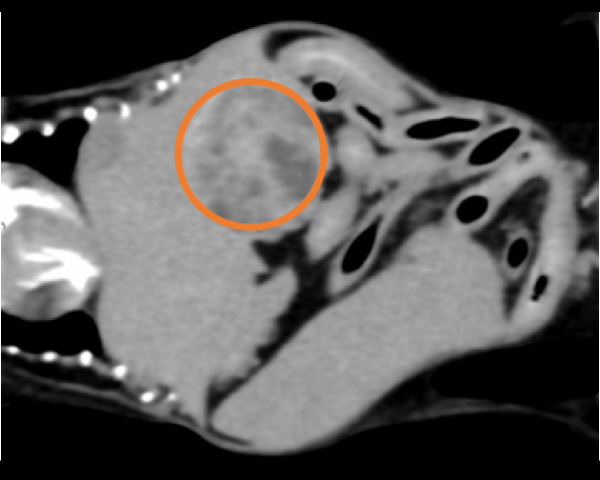

超音波にて副腎腫瘤を確認

造影CT検査にて腫瘤の浸潤を評価